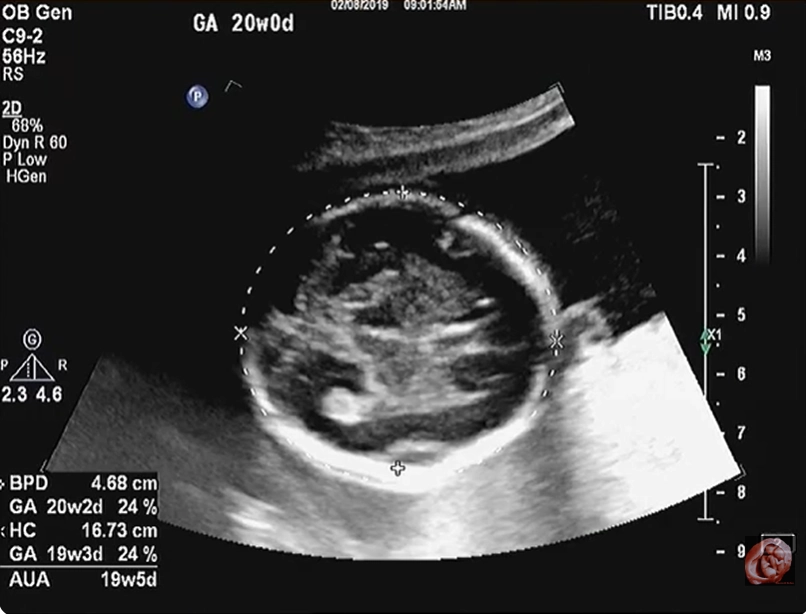

Tật hai mắt xa nhau thai nhi (Hypertelorism)